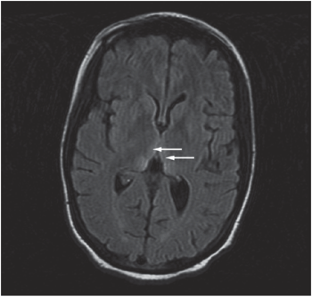

Investigations Physical examination, abdominal ultrasound, fetal ultrasound, brain MRI, magnetic resonance angiography, magnetic resonance venography and cerebrospinal-fluid analysis.

Diagnosis Wernicke's encephalopathy, hyperemesis gravidarum and fetal loss.